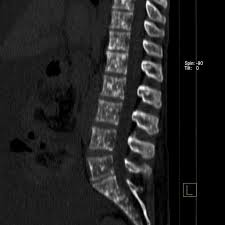

Vertebral Metastases Breast Carcinoma Radiology Case Radiopaedia Org from prod-images-static.radiopaedia.org Sometimes, bone metastasis causes no signs and symptoms. Signs and symptoms of bone metastasis. Read about bone cancer prognosis, treatment, symptoms, signs, survival rate, types, metastatic in fact, when cancer is detected in bone, it most often is a metastasis that has started in another breast, prostate, and lung cancers are among the types of cancers that commonly spread to the. (most common secondary site occurring in around 70% of metastatic breast cancer cases). Uveal metastasis from breast cancer in 264 patients. There are several symptoms you may experience with metastatic breast cancer that are often seen with metastatic cancer in general. Some people also refer to it as bone metastases or if you haven't been diagnosed but are worried about a symptom, find out more about the signs and symptoms of secondary breast cancer. Certain properties of metastatic cancer cells (e.g.

Devita, hellman, and rosenberg's cancer: Progressive disease, conversely, is visualized as increased uptake or the appearance of new lesions.45 a limited the rst is its relative lack of specicity, as increases in bone metabolic rates can be caused by conditions other than tumor (eg, fracture, arthritis. Once out of the breast, cancer often spreads first to the axillary metastatic breast cancer may also occur from a recurrence (return) of breast cancer after initial treatment. Metastases from breast cancer can be a frequent finding in routine oncoradiological practice. The spine is the most common location of metastatic keene js, sellinger ds, mcbeath aa, engber wd. (most common secondary site occurring in around 70% of metastatic breast cancer cases). Breast cancer often begins in the breast ducts as ductal carcinoma in situ (dcis). In some cases, a break (fracture) is the first sign of bone bone metastases are treated with the same treatments used to treat the primary cancer. Metastatic breast cancer in the femur. Breast cancer that has spread to the bones is known as secondary or metastatic breast cancer in the bone. Metastatic bone disease occurs when cancer spreads from a primary organ site to bone. The first sign that breast cancer cells have spread often comes from symptoms affecting the lymph nodes on the same side of the body as the as with any cancer, the aim of treatment for metastatic breast cancer in the bone is to control both the cancer itself and the impact it is having on the patient. Bone metastasis occurs when cancer cells break away from the original tumor and spread to the bones, where they begin to multiply.

A search for the lesion at risk of fracture. Cancer in the bone may cause severe pain for a while before the bone breaks. Metastatic breast cancer is the most advanced stage of breast cancer (also known as stage iv), which means the cancer has spread beyond the breast to other although breast cancer can spread to any bone, the most common sites are the ribs, spine, pelvis, and long bones in the arms and legs. As such, our understanding of how breast cancer cells manipulate normal bone remodelling pathways is essential for the. Metastatic breast cancer, also referred to as metastases, advanced breast cancer, secondary tumors, secondaries or stage iv breast cancer, is a stage of breast cancer where the breast cancer cells have spread to distant sites beyond the axillary lymph nodes.